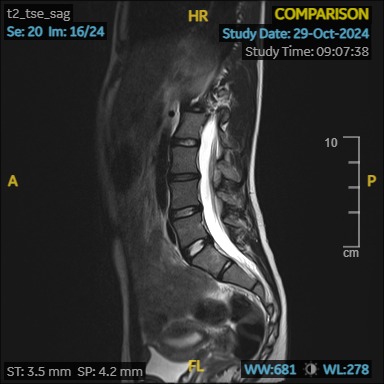

– Imaging Tests: X-rays, MRI, or CT scans may be used to determine the degree and location of the curve.